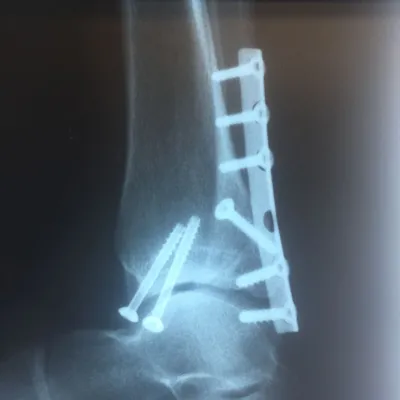

Preop and Postop Trimalleolar Fracture with Fixation of Posterior Malleolus Fracture

Pre and postop Trimalleolar Fracture without FIxation of Posterior Malleolus

Both the lateral and medial malleolus with fractures with the lateral malleolar fracture classified as a Weber B (at the level of the ankle joint) and the medial malleolar fracture almost transverse (Left x-ray). This is indicative of a Supination External Rotation (SER IV) injury. The fractures are repaired using open reduction with internal fixation (ORIF) technique and fixated with screws and a surgical fractue plate located at the fibular (Right x-ray).